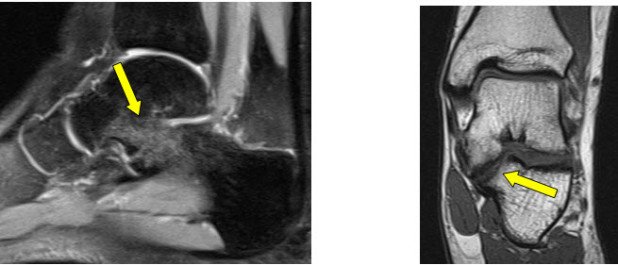

Neben den konventionellen Röntgenbildern, führten wir eine Magnetresonanz-Tomographie (MRI) Untersuchung durch, um das untere Sprunggelenk genauer beurteilen zu können. Auf der Innenseite des Gelenkes konnte auf beiden Seiten eine abnormale Verbindung zwischen dem Fersen (Calcaneus)- und dem Sprungbein (Talus) nachgewiesen werden (Abb. 1+2).